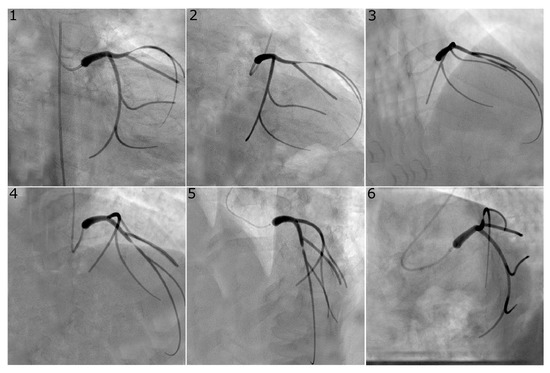

Figure 3.

Virtual angiogram for all views of the left coronary system with an eccentric stenosis of type “8040” in the LAD. Views , and were used to reconstruct this vessel as they are usually selected in the catheterisation laboratory since they avoid vessel overlap and excessive foreshortening for the vessel of interest.

Figure 2 and Figure 3 show representative examples of virtual angiograms generated for the two coronary arteries considered in this study. Figure 2 shows the case in which a concentric stenosis, of diameter reduction, affects the LCX. This case is included here for theoretical interest as it allows for an appreciation of the severity of a stenosis of this diameter reduction, but it is of smaller concern to the clinical community, due to the certainty of its severity. Figure 3 shows the case in which the LAD is affected by stenosis, this time of the eccentric type, with diameter reductions of and in the two orthogonal directions. This case shows how eccentric stenoses can appear differently in different views, and showcases that the choice of the view pair can result in either underestimation or overestimation of the severity of the stenosis (thus, overestimating or underestimating the radius, respectively).

The accuracy of the reconstruction of the vessel radius at the stenosis location was expected to be closely related to the accuracy of the computed vFFR. Greater variation of this metric was observed with choice of image pairs with a range of maximum absolute error from 0.07 mm to 0.20 mm for the LCX and 0.15 mm to 0.24 mm for the LAD. There was no clear relation between absolute error and the stenosis severity; as a result, the percentage error in the stenosis radius tended to increase for larger-percentage diameter reductions. The error in stenosis reconstruction was typically larger for cases with eccentric stenosis, as expected, due to the different views showing different vessel radii depending on the orientation of the eccentricity. Indeed, as visible in Figure 3, which reports a case of eccentric stenosis in the LAD, the vessel radius appears significantly larger in views 4 and 5, compared to, for example, views 1 and 2. Our software estimates the vessel radius from each of the two angiographic views and averages the two values; the reconstructed local lumen will have a circular shape with a radius equal to that averaged value. It is possible for two views to simultaneously fail to capture the peak value of stenosis, thus obtaining a larger error in the radius estimation and therefore in the vFFR.